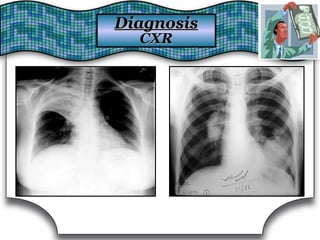

Chest X Ray (CXR)Chest X Ray (CXR)

Chest RadiographChest Radiograph Suggestive DiagnosisSuggestive Diagnosis

Cardiomegaly, increasedCardiomegaly, increased

pulmonary vascular distributionpulmonary vascular distribution

Chronic heart failure, mitral valve stenosisChronic heart failure, mitral valve stenosis

Cavitary lesionsCavitary lesions Lung abscess, TB, necrotizing carcinomaLung abscess, TB, necrotizing carcinoma

Diffuse alveolar infiltratesDiffuse alveolar infiltrates Chronic heart failure, pulmonary edema, aspirationChronic heart failure, pulmonary edema, aspiration

Hilar adenopathy or massHilar adenopathy or mass Carcinoma, metastatic disease, infectionCarcinoma, metastatic disease, infection

HyperinflationHyperinflation COPDCOPD

Lobar or segmental infiltratesLobar or segmental infiltrates Pneumonia, thromboembolism, obstructing carcinomaPneumonia, thromboembolism, obstructing carcinoma

Mass lesion, nodules, granulomasMass lesion, nodules, granulomas

Carcinoma, metastatic disease, Wegener'sCarcinoma, metastatic disease, Wegener's

granulomatosis, septic embolism, vasculitidesgranulomatosis, septic embolism, vasculitides

Patchy alveolar infiltratesPatchy alveolar infiltrates

Bleeding disorders, idiopathic pulmonaryBleeding disorders, idiopathic pulmonary

hemosiderosis, Goodpasture's syndromehemosiderosis, Goodpasture's syndrome